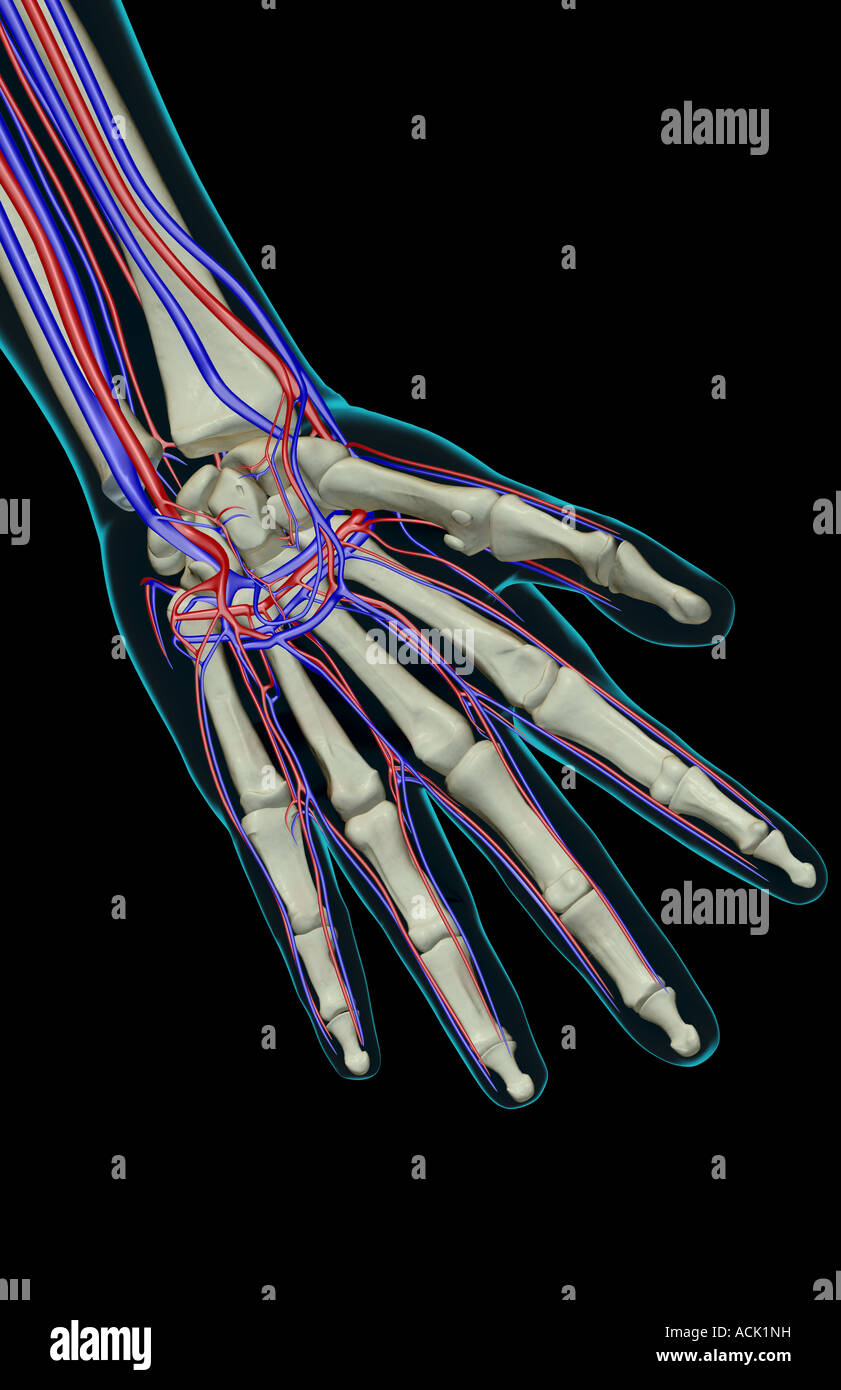

The blood supply of the hand Stock Photohttps://www.alamy.com/image-license-details/?v=1https://www.alamy.com/stock-photo-the-blood-supply-of-the-hand-13174924.html

The blood supply of the hand Stock Photohttps://www.alamy.com/image-license-details/?v=1https://www.alamy.com/stock-photo-the-blood-supply-of-the-hand-13174924.htmlRFACK1NH–The blood supply of the hand